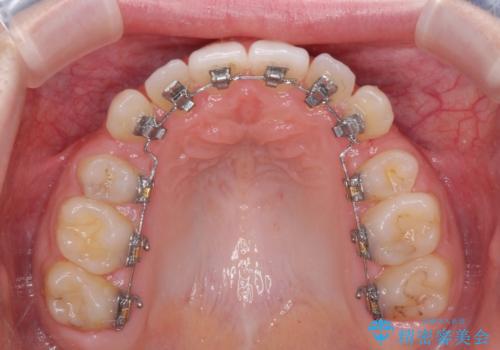

- 矯正装置

- ハーフリンガル

- 前歯のデコボコと八重歯を気にして来院された患者様です。

目立たない装置を希望されたので、上顎が裏側装置のハーフリンガルを選択し、左右上顎小臼歯1本ずつを抜歯して、矯正治療を行うこととしました。